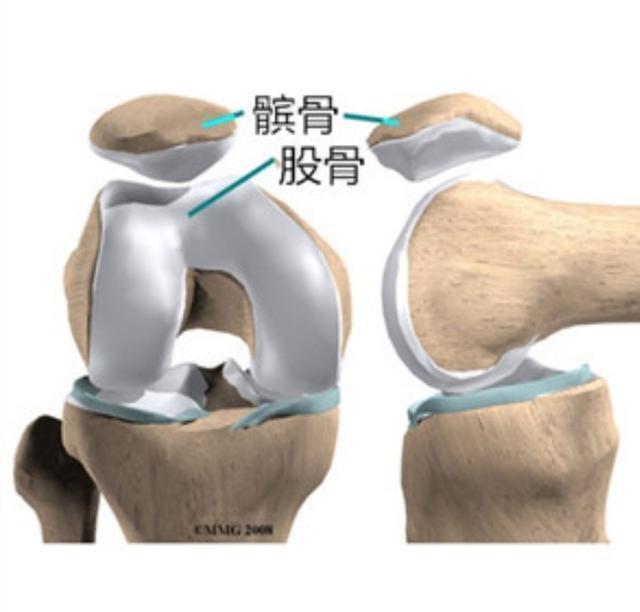

在我们骨科门诊啊,膝关节疼痛,是五大常见症状之一。来骨科门诊看膝关节疼痛的不仅有六七十岁的老年人,四五十岁中年人,还有很多二三十岁的青年人,他们其中有将近一半出现以下的症状,就是膝关节在上下楼梯或者蹲起的时候,有困难、有僵硬、有疼痛感,但是大多数时候平地走路倒没什么感觉。很多人非常不解,这到底是什么原因?其实这在我们膝关节领域,非常常见,看懂了这幅解剖图,您就知道原因了。

我们的膝关节实际上有三块骨头组成,分别是大腿骨,小腿骨,还有膝盖正面的、圆形的髌骨。髌骨是我们每个人都能摸到的,你用手放在你的膝盖正前方就能触摸到一个圆形的,像盖子一样的圆骨头,只要你的大腿肌肉是放松状态,那么髌骨就是可以左右推动的。那么既然是三块骨头,它们就构成了两个不同的接触面。一个呢,很好理解,是大腿和小腿骨之间的接触面,这个关节面是让我们负重用的。不论我们是站着、走路、跳跃,只要有体重压在膝盖上,这个关节面就承担压力。而我们人体膝关节的结构,决定了内侧关节受力多,约占整个重量的60?外侧关节面受力少,约占40?所以往往都是膝盖内侧磨损的快,内侧关节间隙,首先出现狭窄,所以很多人膝关节炎,刚开始的症状会有膝盖内侧的疼痛,久而久之,也会出现O型腿,也叫膝内翻,这就是因为膝盖内侧的软骨等结构已经被磨损殆尽。

如图所示,内侧关节缝隙比外侧变得狭窄了,膝盖的外观也就变成罗圈腿了。当出现这些症状的时候,我们就会开始出现走路疼痛。一般都是先有内侧疼,然后逐渐发展到整个关节都疼。等到走平地都不能走了,每一步都疼的时候,往往这个时候就需要做保膝手术或关节置换等手术治疗了。除此之外呢,我们的膝盖还有一个关节面,叫做髌股关节。也就是刚才我们摸的那个圆骨头深部的软骨面。这个部位比较特殊,当我们伸直腿,也就是走路的时候,这个关节面的压力是比较小的,甚至软骨和软骨之间都是不接触的。这是为什么刚才我们在伸直并放松大腿肌肉的时候,髌骨可以推动的原因。

但是当我们膝盖弯曲的时候,我们发现髌骨无法推动了,这是因为当弯曲膝盖的时候,髌骨被压在了股骨上,两个关节面的软骨开始受压,摩擦。所以说,当我们在上下楼梯,蹲起,坐着起来,爬山爬坡等等,需要弯曲膝盖使劲的动作的时候,髌股关节面会承担负荷,久而久之会产生磨损。当我们的大腿和小腿之间的关节面保存的还可以,而髌股关节之间的关节面磨损的比较严重的时候,我们就会开始出现上下楼梯疼,爬山爬坡疼,蹲下起来疼,但是走平地不疼的现象。